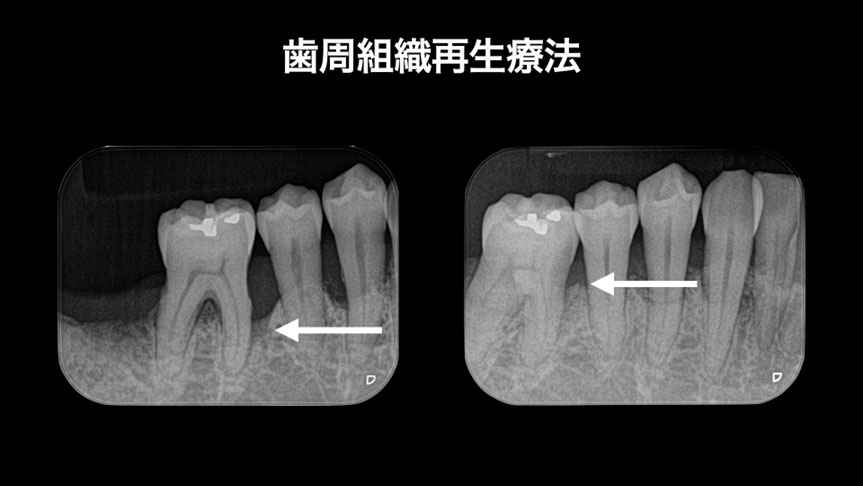

■歯周組織再生療法

歯周病で失われた骨や歯周組織の改善を図ります

歯周病で抜歯と言われた歯の保存

before    after